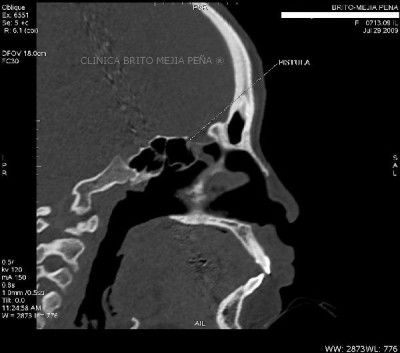

Fístula LCR coronal